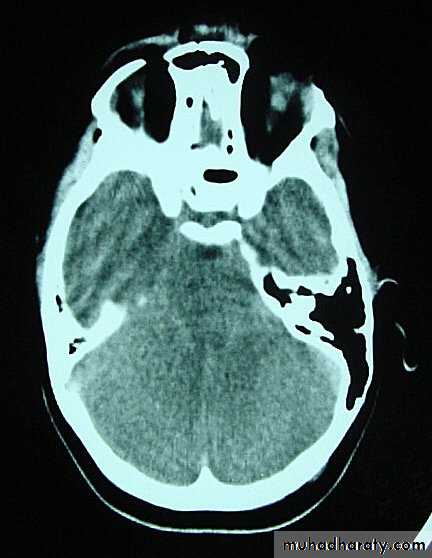

d. Subarachnoid Haemorrhage

Trauma is the commonest cause of SAH although aneurysms are the most common cause of spontaneous SAH.Traumatic SAH is managed conservatively.